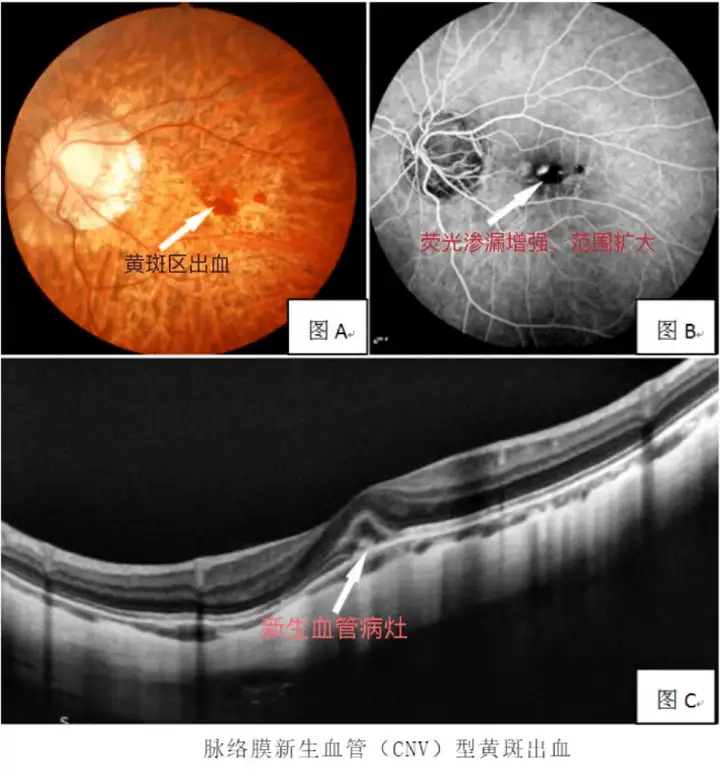

更危险的是,欧堡眼底相机检查发现其视网膜已出现严重变性,伴随玻璃体浑浊和飞蚊症等高度近视并发症。"他的视网膜就像布满裂痕的窗户,一次剧烈晃动就可能视网膜脱离。"爱尔眼科视光医生蒋主任直言,若不及时干预,病理性眼轴增长将把失明风险推向悬崖边缘。

刘先生的案例揭开了高度近视群体的生存困境。当近视超过600度,青光眼、黄斑病变等致盲风险骤增;超过1000度者,视网膜脱离发生率是常人的10倍。而像刘先生这样的2400度的近视患者,连骑车这样的日常活动都成奢望。